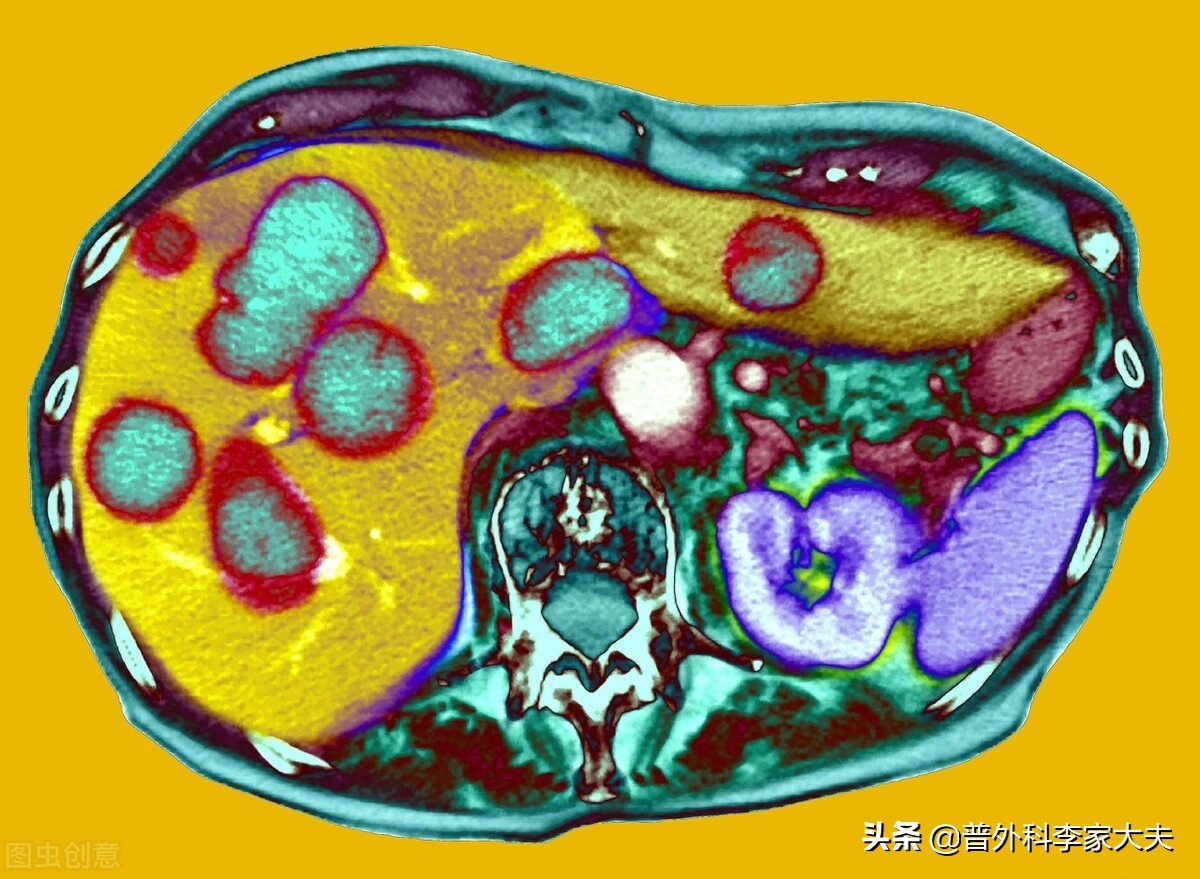

肝癌起病隐匿,早期缺乏典型症状,加上我国未广泛开展肝癌的普查工作,因此,肝癌患者的发现多数是因出现临床就医才发现的。但有典型临床症状才发现的肝癌患者,多数疾病已经进入了肝癌晚期。但不管如何,延长生命与提高生活质量,仍然是所有肝癌晚期患者的追求,饮食是既是人体正常生理需求的必需,也是保证肝癌营养来源与抗癌治疗的基础,但不健康的饮食,对肝癌晚期患者来说,也是不利于疾病恢复,甚至会危及患者生命。如何饮食才有利于肝癌晚期的健康呢?总结起来,肝癌晚期患者应该注意以下几方面情况:

肝癌